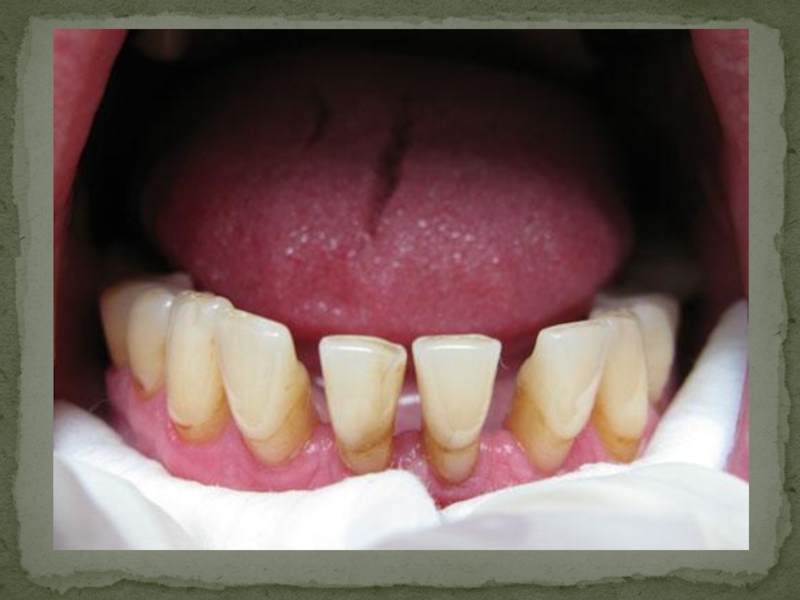

Слайд 10ШИНИРОВАНИЕ ФРОНТАЛЬНОЙ ГРУППЫ ЗУБОВ

ШИНИРОВАНИЕ ФРОНТАЛЬНОЙ ГРУППЫ ЗУБОВ